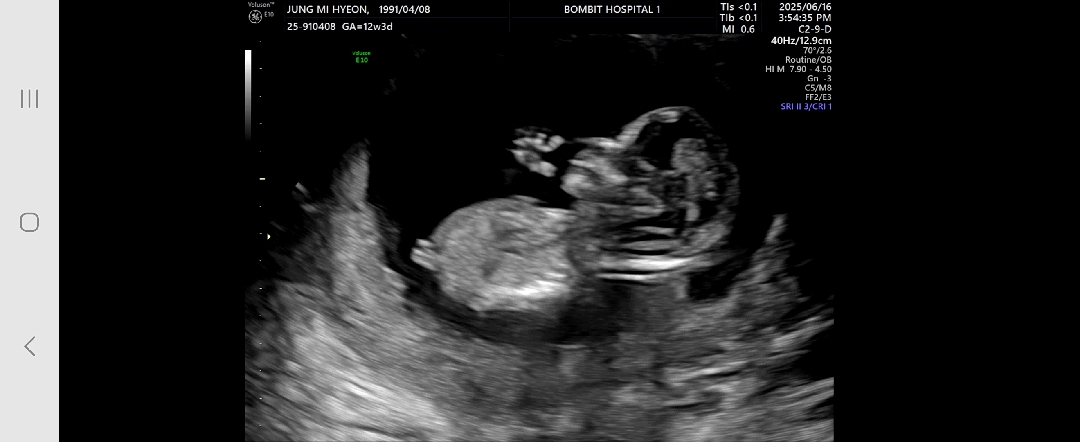

각도법 고수님들~~~ 사진 한번만 봐주세요! 아들일까요? 딸일까요? 아이가 평평하게 누워있는 상태가 아니다보니 초보엄마는 가늠하기 어렵네요 ㅠㅠ